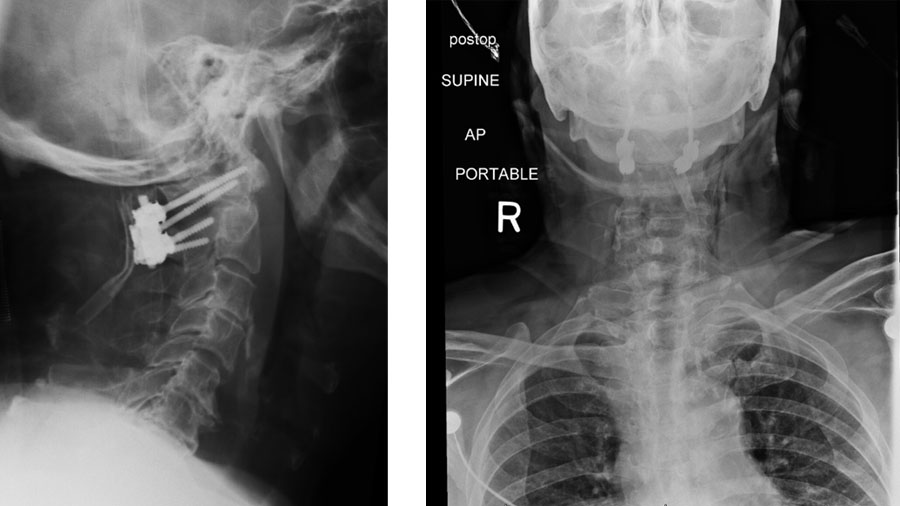

The first step in managing atlantoaxial instability is deciding whether nonoperative care is a reasonable option.3 In select cases, typically stable fractures without neurological deficit, patients may be managed with a rigid collar or halo, though nonunion is a frequent concern, especially in elderly or osteoporotic individuals.4–6 When there is clear instability, progressive deformity, or neurological compromise, surgery is the more reliable path (Figure 1).

In most cases, posterior fusion is required, and the choice between transarticular and Goel–Harms fixation depends on vertebral artery anatomy, reducibility of the joint, and surgeon preference.28 Once operative indication has been determined, listed below is one potential decision-making algorithm regarding surgical technique (Figure 2).